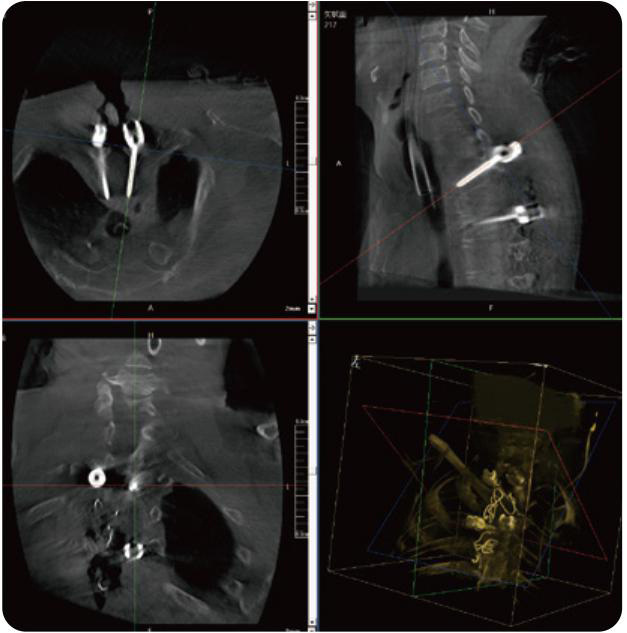

PL300B可應(yīng)用于多節(jié)段脊柱外科手術(shù),輔助醫(yī)生定位病灶部位,為脊柱外科手術(shù)(經(jīng)皮椎體成形術(shù)、椎弓根螺釘內(nèi)固定術(shù)等術(shù)式)提供術(shù)前手術(shù)流程規(guī)劃、入釘位置、角度可視化引導(dǎo),模擬仿真入釘輔助。

PL300B搭配普愛醫(yī)療自主研發(fā)生產(chǎn)的平板3D C形臂,借助一體化自適應(yīng)配準(zhǔn)( 軌跡配準(zhǔn))技術(shù),通過(guò)追蹤C(jī)形臂三維采集軌跡,自動(dòng)完成圖像坐標(biāo)建立和系統(tǒng)坐標(biāo)配準(zhǔn)。配準(zhǔn)精度更高,操作步驟少,系統(tǒng)運(yùn)作效率高。